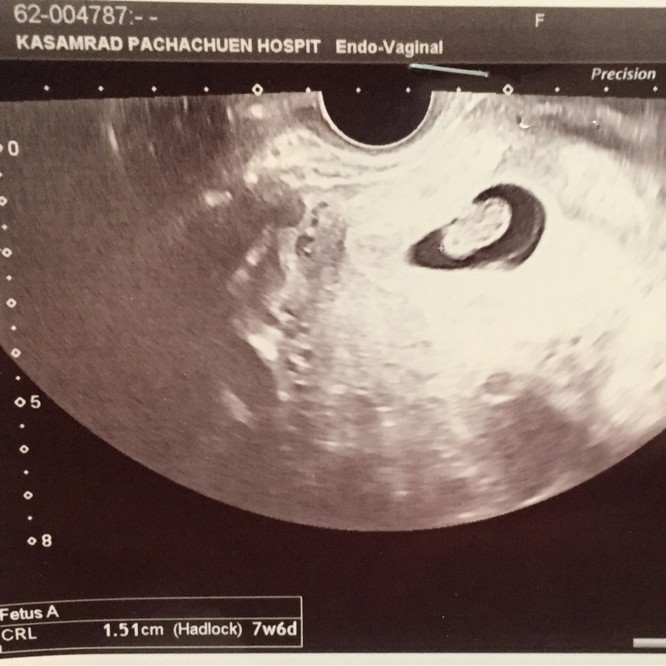

6 ธ.ค. 63 ค่ะ | ซาวด์ตอน 10w 3d